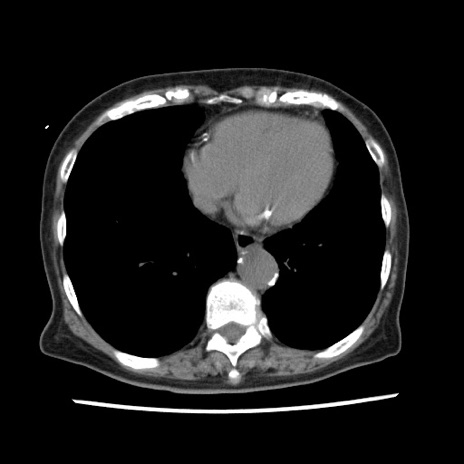

冠状断像

【症例】80歳代女性

【主訴】腹痛

【現病歴】8時間前から腹痛あり来院。

【既往歴】糖尿病、脂質異常症、子宮体癌にて子宮全摘術

【身体所見】意識清明・会話良好だが腹痛で苦悶様、全腹部にわたって反跳痛と圧痛あり

【データ】WBC 13600、CRP 0.14、LDH 224、CK 90